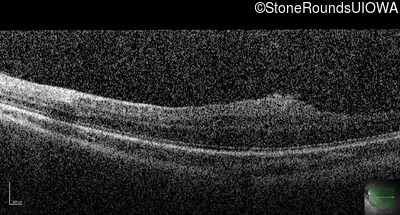

This 9 year old male was noted to have some crossing of his eyes at 2 months of age and the eye exam which followed identified a retinal lesion in the right eye. When he was six years old an epiretinal membrane was noted in his left eye. Two years later it was decided that it was a thin hamartoma in that eye as well. He underwent neuroimaging at age 7 which identified bilateral acoustic neuromas.

| Age at visit: 8 years |

| Age at visit: 10 years |